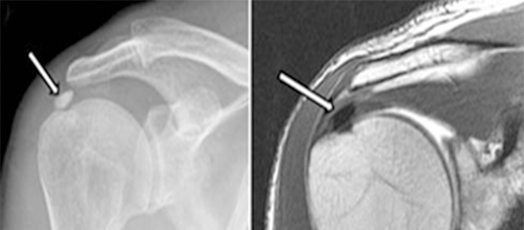

어깨 힘줄에 석회질이 생성되면서 염증이 발생하고 그것이 돌처럼 굳어지면서 심한 통증을 일으키는 질환입니다.

석회성 건염의 원인은 정확히 밝혀지진 않았으나 칼슘의 배출 과정에 문제가 있어서 어깨 인대 부위에 석회가 침착하는 것으로 알려져 있습니다. 어깨 힘줄에 혈류가 감소해 산소 분압이 떨어지면서 힘줄 세포가 연골 세포로 변해 석회질이 침착된다는 가설도 있습니다. 침착된 석회질은 하나 혹은 여러 개가 한 번에 생기기도 하고, 1mm~3cm 정도 다양한 크기로 침착됩니다. 주로 힘줄 세포가 괴사된 부위에 석회가 차서 생기고 어깨의 과도한 사용도 원이이 될 수 있습니다.